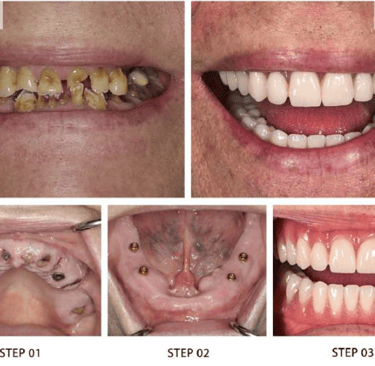

Our Signature Implant Services

Restoring Smiles with Precision and Care

At Dr. Wadkar’s Dental Clinic, we specialize in replacing missing teeth with solutions that look, feel, and function exactly like natural teeth. Using the latest Digital Implant Workflow, we ensure every procedure is minimally invasive and highly predictable.

2. Full Mouth Rehabilitation

For patients with significant tooth loss, we offer comprehensive full-arch restorations. Utilizing techniques learned from masters, we stabilize your entire smile with a few strategically placed implants.

● The Benefit: Eat what you want, speak clearly, and look years younger with a stable, permanent smile.